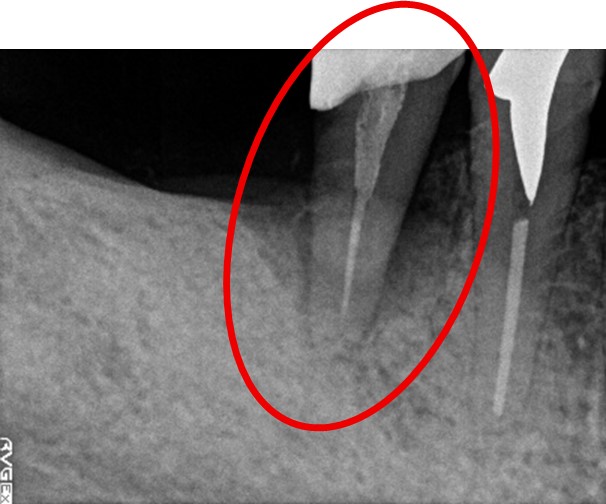

治療内容

歯根の周りの骨が全く無い状態でしたので、保存することができず抜歯しました。3本歯がないところに2本インプラントを埋入しました。

Before

※赤丸を抜歯しました。